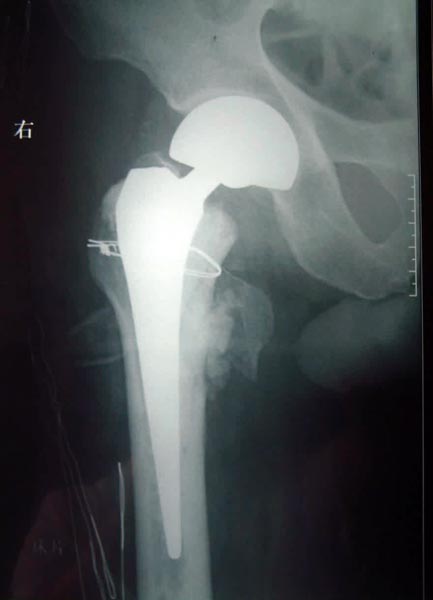

患者82岁,男性,股骨粗隆间粉碎骨折,伴有冠心病、骨质疏松。

采用小切口微创双极人工股骨头置换术置换术,骨折块用钢丝固定。

术后5天下地活动,恢复满意。